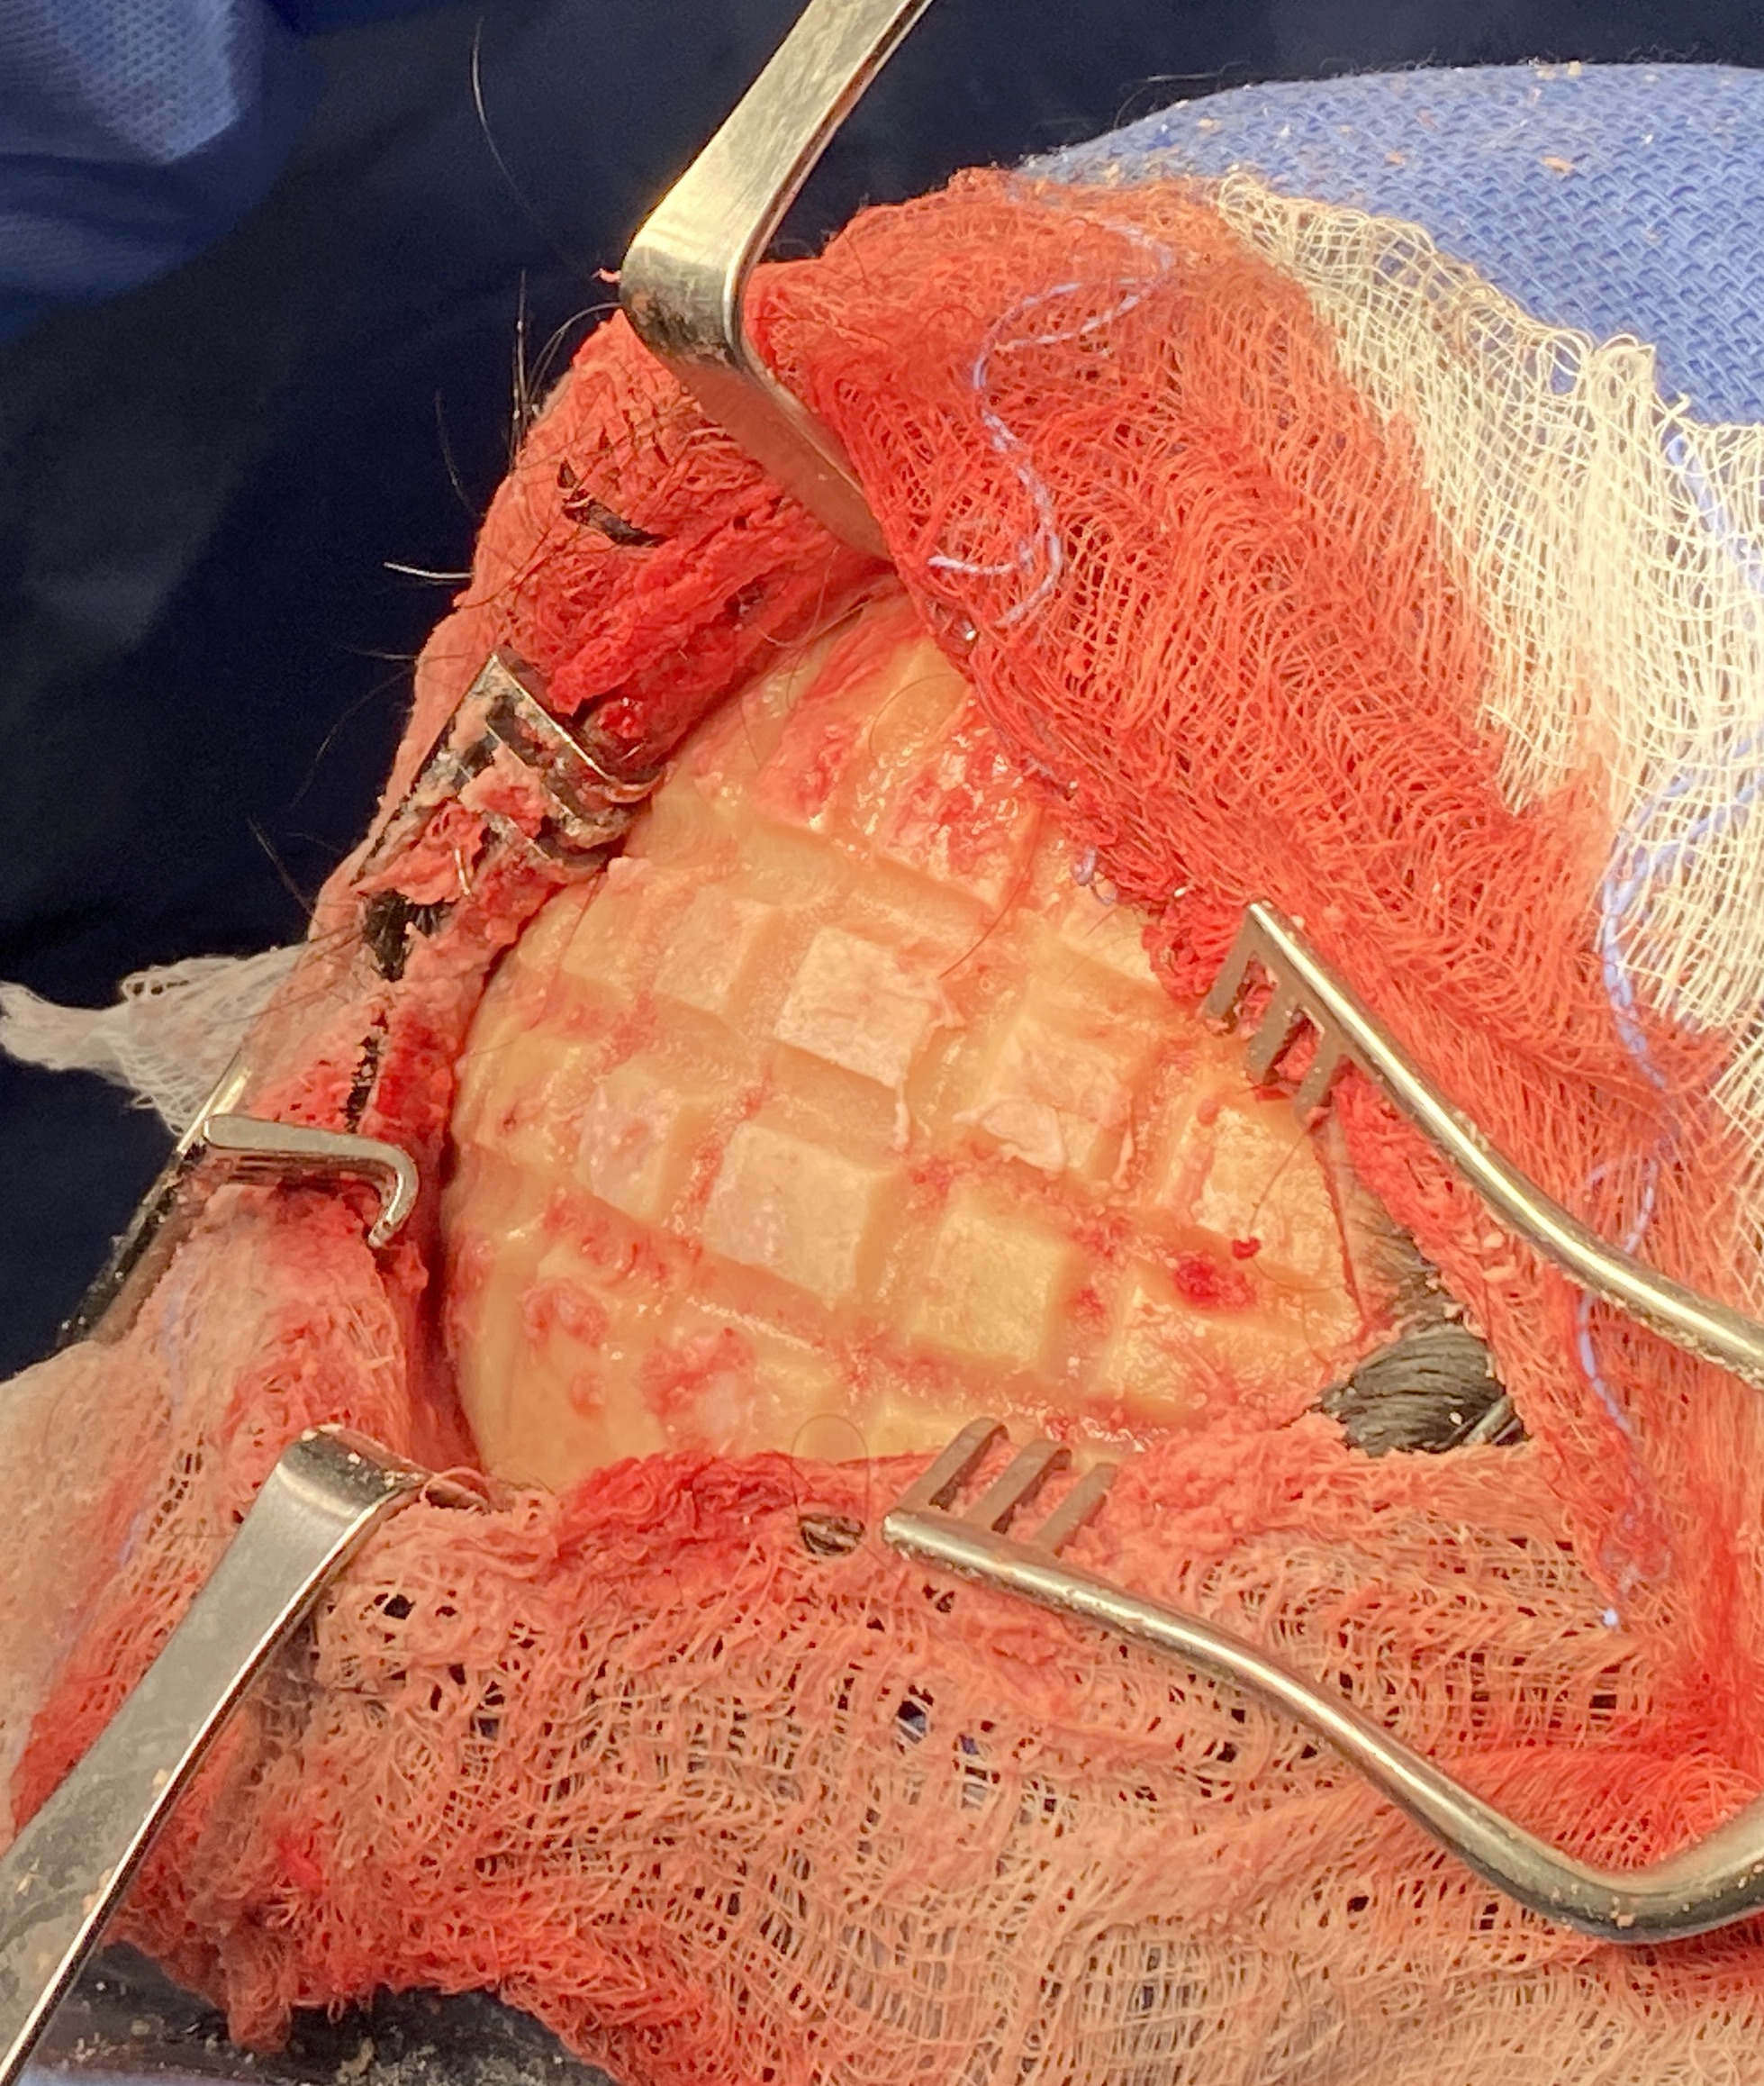

Desire for reduction in height of top of head.

Top of head skull reduction by removal of the outer cortical bone layered by a grid burring technique.

Desire for reduction in height of top of head.

Top of head skull reduction by removal of the outer cortical bone layered by a grid burring technique.